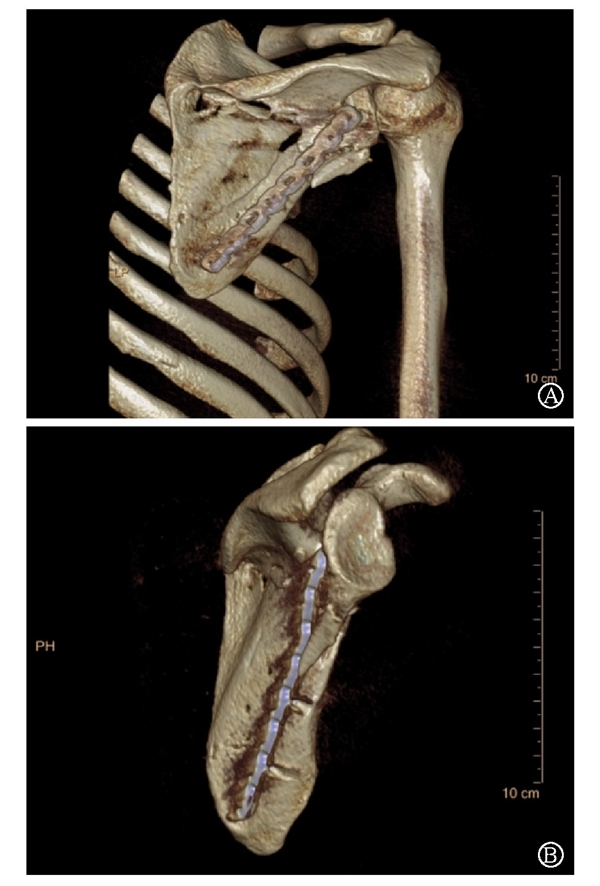

术中采用钢板固定肩胛颈内下方骨折块,肩胛骨体部骨折固定采用缝线辅助固定技术,骨折端以Nice结固定。术后CT三维重建显示骨折复位满意,固定良好(图22)。

图22 术后CT三维重建示肩胛骨骨折复位满意,内固定位置良好 图A:肩胛骨后面观;图B:肩胛骨侧面观